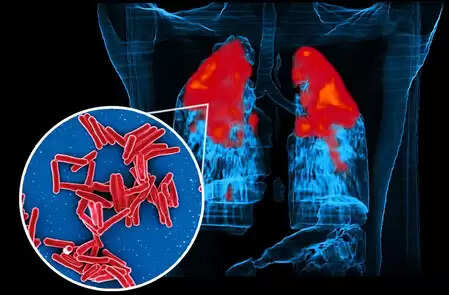

आईआईटी बॉम्बे के अध्ययन से पता चला कैसे टीबी बैक्टीरिया एंटीबायोटिक दवाओं को देते हैं 'धोखा'

नई दिल्ली, 3 दिसंबर (आईएएनएस)। क्षय रोग (टीबी) दशकों से एक गंभीर वैश्विक स्वास्थ्य समस्या बना हुआ है। आईआईटी बॉम्बे ने इस पर एक स्टडी की है, जिससे पता चलता है कि माइकोबैक्टीरियम ट्यूबरकुलोसिस नामक जीवाणु अपनी ऊपरी फैट कोटिंग (वसा परत) को बदलकर एंटीबायोटिक उपचार से बचते-बचाते लंबे समय तक शरीर में बने रहते हैं।

केवल 2023 वर्ष में दुनिया के लगभग 1 करोड़ से अधिक लोग टीबी से ग्रसित हुए और 12 लाख से अधिक लोगों की इससे मृत्यु हो गई। भारत में इसके संक्रमितों की तादाद सबसे ज्यादा है; यहां 2024 में 26 लाख से अधिक रोगी पाए गए।

केमिकल साइंस नामक जर्नल में प्रकाशित इस अध्ययन में इस बात की खोज की गई कि औषधि से अप्रभावित रहने का रहस्य जीवाणु की झिल्लियों (मेम्ब्रेन्स) में छिपा हो सकता है—ये झिल्लियां वसा (फैट्स) या लिपिड से बनी जटिल भित्तियां होती हैं जो कोशिका (सेल्स) की रक्षा करती हैं।